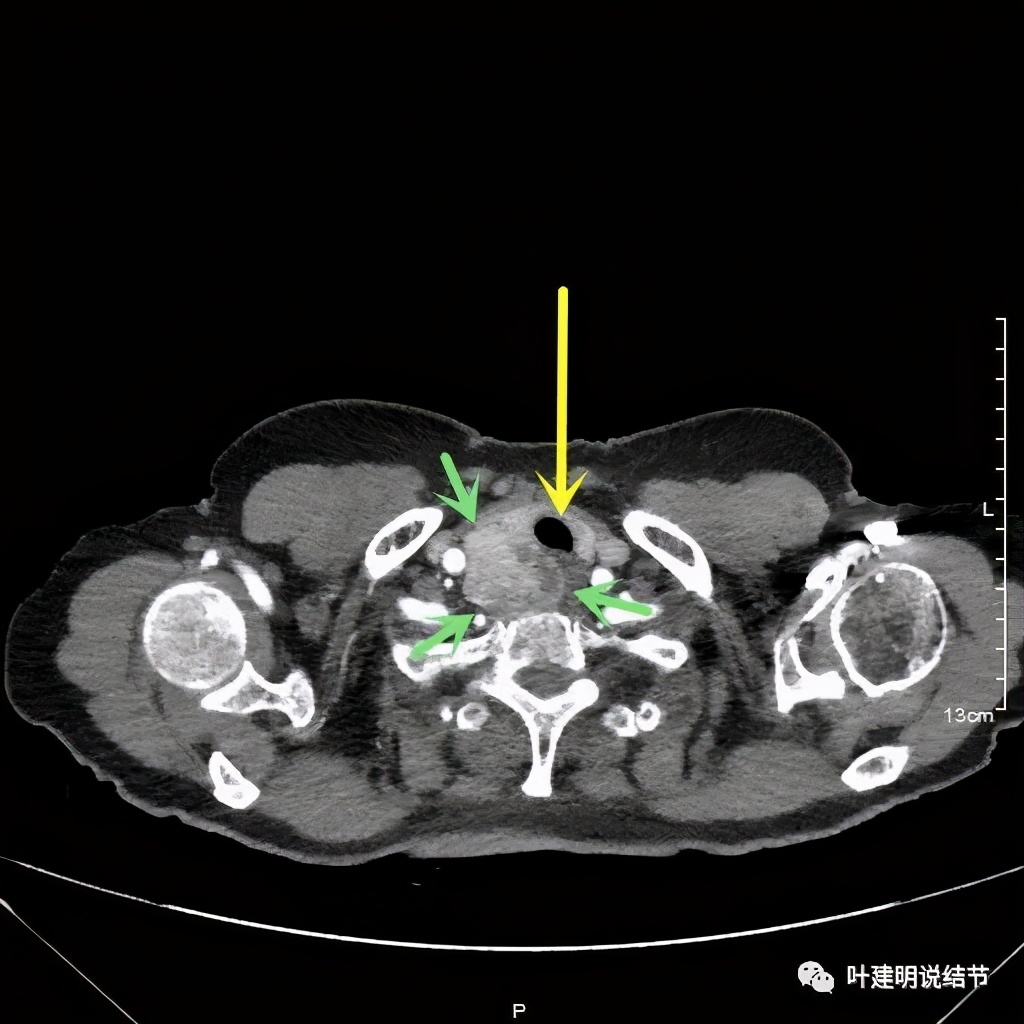

上图红色示肿瘤,黄色示气管,粉色示肿瘤与气管关系密切,而且肿瘤密度不均杂乱

上图红色示肿瘤,黄色示气管,粉色示肿瘤与气管关系密切,桔色示左无名静脉,蓝色示上腔静脉,而且肿瘤密度不均杂乱

上图红色示肿瘤,黄色示气管,桔色示左无名静脉,蓝色示上腔静脉,而且肿瘤密度不均杂乱